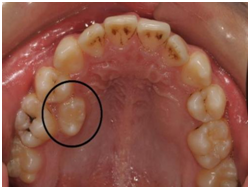

成员三:异位萌出的前磨牙

上图圈出来的牙齿就是这位成员了,他们往往是由替牙障碍引起的。乳磨牙过早脱落,新长出的六龄齿没有了前面的阻挡,逐步向前移动,本该在这个位置上长出来的恒牙被迫从其他位置萌出。对这种情况置之不理,则三颗牙齿之间的间隙会发生食物嵌塞,进而形成龋坏,严重的龋坏会造成三颗牙都无法保留。所以,乳牙发生龋坏后要及时治疗,乳磨牙因无法保留而拔除后也应进行积极的间隙管理,为继承的恒牙留出足够的生长空间。